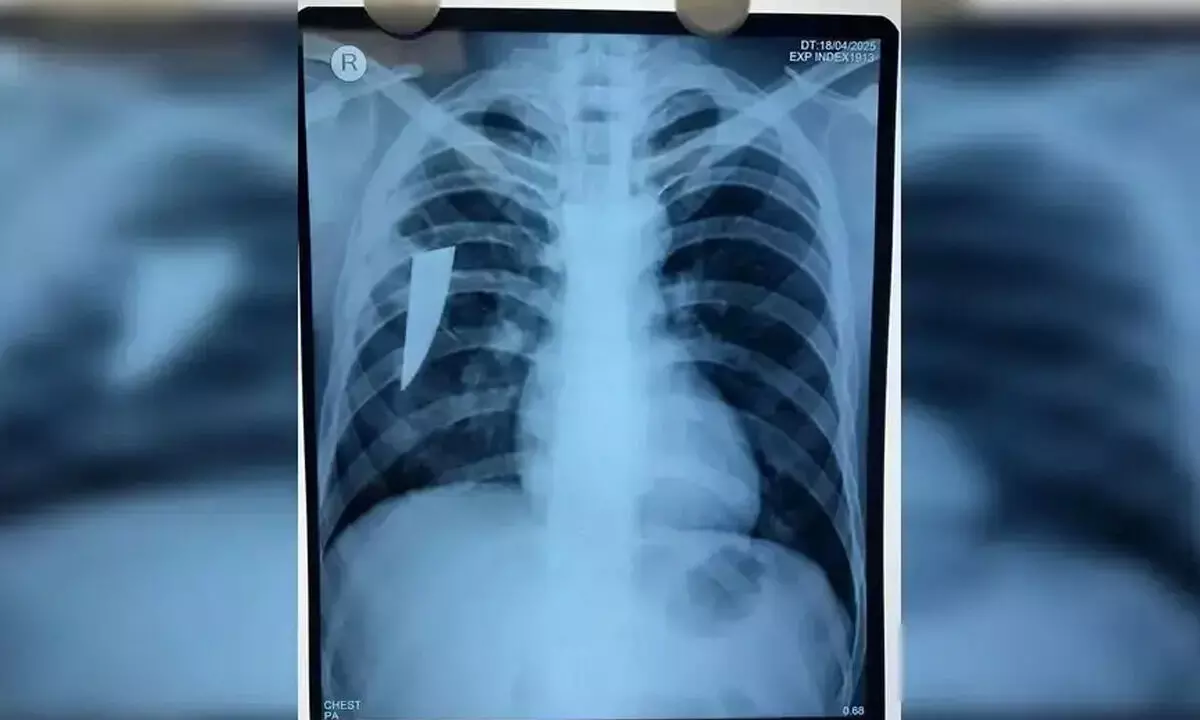

Berhampur: A team of doctors in MKCG Medical College and Hospital here removed an 8-cm-long broken piece of knife from the lungs of a 24-year-old man, an official said on Thursday. The broken knife piece was in the body of the man for the last three years after a stabbing incident.

A group of doctors, led by Sarada Prasanna Sahoo, Associate Professor of Cardiothoracic and Vascular Surgery (CTVS) department, removed the sharp metallic foreign object from the lungs of Santosh Das of Kabisurya Nagar by conducting the right thoracotomy operation on Tuesday, the official said. The length of the steel and sharp knife was around 8 cm, and its width and thickness were 2.5 cm and 3 mm, respectively, said Sahoo. The condition of the patient was good and he was now in the intensive care unit (ICU) under observation, the doctor said. The piece of knife entered his body after he was stabbed by a miscreant in Bangalore, three years ago, when he was working as a labourer. He was stabbed on the left side of his neck. He was cured after being treated at Bangalore and there was no complaint for about two years.

About a year ago, he suffered from dry cough and fever, raising fears of tuberculosis. He has also completed nine-month treatment of tuberculosis, said the doctor. Family members of the patient rushed him to medical college and hospital here when he started getting blood in his cough. He came to the hospital here on April 19. The foreign object was found in his body after conducting an X-ray. It was detected in his right lung after conducting the CT scan and bronchoscopy, said Sahoo. “A group of around eight doctors in CTVS and anaesthesia departments, nursing officers and para-medical staff conducted the surgery and removed the sharp metal piece successfully,” he said.